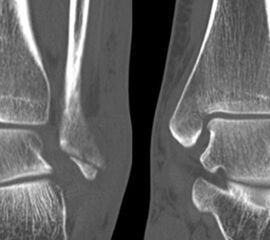

Liegt eine Fraktur des oberen Sprunggelenks vor, ist sowohl zur Entscheidung für ein konservatives oder operatives Vorgehen, als auch zur Operationsplanung, ein ausreichendes Verständnis der Fraktur und ihrer Morphologie notwendig. Insbesondere bei komplexen Verletzungen ist dafür die konventionelle Röntgenaufnahme in vielen Fällen nicht ausreichend. So konnten z.B. Black et al. zeigen, dass die operative Strategie zur Versorgung von OSG-Frakturen in 24% basierend auf einer zusätzlichen CT-Bildgebung relevant geändert wurden 7. Dies betraf die Lagerung, die Wahl des Zuganges und die Art der osteosynthetischen Versorgung. Besonders häufig änderte sich das Vorgehen bei Verletzungen des medialen (21%) und des posterioren Malleolus (15%). Darüber hinaus führten dislozierte (dislozierte Frakturen 31% vs. nicht-dislozierte Frakturen 20%) oder komplexe Frakturen (Trimalleolar-Frakturen 29% vs. Unimalleolar-Frakturen 10%) besonders häufig zu relevanten Änderungen des operativen Vorgehens. Die Computertomographie ist daher, insbesondere bei Bi- und Trimalleolar-Frakturen, essentiell für das Verständnis der Fraktur und somit für die Planung und Durchführung der Operation. In Abbildung 4 und 5 sind exemplarisch ein Röntgen- und ein CT Befund gegenübergestellt.

Seit einer Untersuchung von Nelson und Jensen aus dem Jahre 1940 wird allgemein akzeptiert, dass die Indikation zur Osteosynthese des Tibiahinterkantenfragments nur dann besteht, wenn die Größe mehr als ein Drittel (nach zahlreichen Autoren auch ein Viertel) der Gelenkfläche beträgt (Abbildung 15) 25. Dieses bis heute allgemeinakzeptierte Vorgehen basiert auf der Beobachtung von lediglich acht unterschiedlich versorgten Patienten. Seither gibt es keine weiteren klinischen Studien, die dieses Vorgehen stützen. Mittlerweile gibt es allerdings zunehmend Hinweise, dass bei der Versorgung des posterioren Malleolus viele andere Faktoren eine wichtige Rolle spielen 26. Da an der Tibiahinterkante das Lig. tibiofibulare posterius ansetzt (Abbildung 16), wird durch die offene Reposition und Stabilisierung die Integrität und die physiologische Spannung der hinteren Syndesmose rekonstruiert (Abbildung 17). Dies ist entscheidend für die anatomische Reposition der Fibula in der Tibiainzisur.